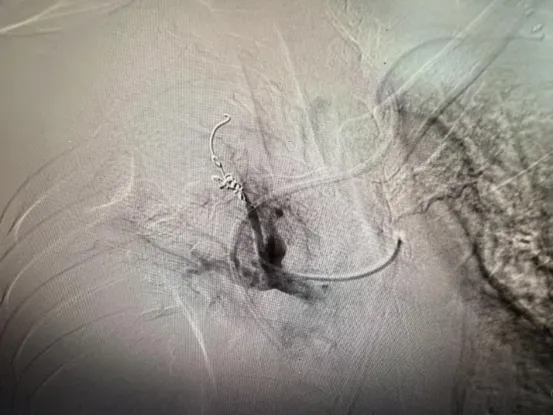

造影发现肺动脉假性动脉瘤并出血(红圈标记)

栓塞后出血停止